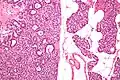

Micrograph of a parathyroid adenoma (left) and normal parathyroid gland (right). H&E stain.